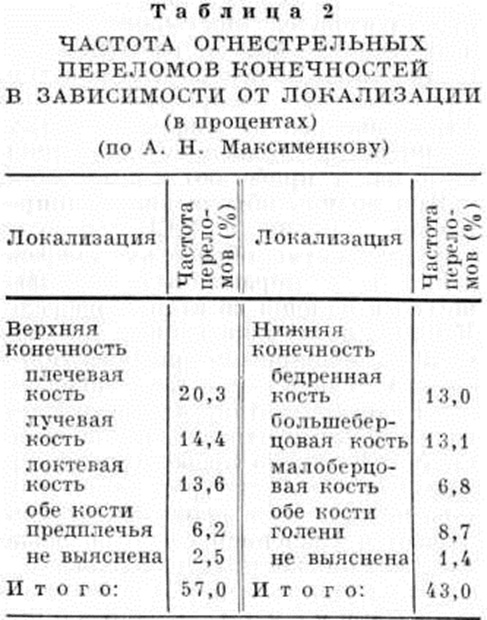

Переломы в военно-полевых условиях. В военное время чаще встречаются огнестрельные Переломы костей, которые классифицируют по локализации ранения, виду ранящего снаряда (пулевые, осколочные и др.)> характеру ранения (сквозные, слепые, касательные), виду Переломы (дырчатые, краевые, вколоченные, крупнооскольчатые, мелкооскольчатые, поперечные, косые, продольные), а также по сопутствующим повреждениям мягких тканей, крупных сосудов, нервов, суставов. Ранения конечностей, сопровождающиеся переломами, по частоте преобладают над ранениями других локализаций. По данным А. Н. Максименкова, огнестрельные переломы верхних конечностей наблюдаются в 57%, нижних — в 43% (таблица 2). Изолированные, оскольчатые и многооскольчатые Переломы преобладали над краевыми и дырчатыми.